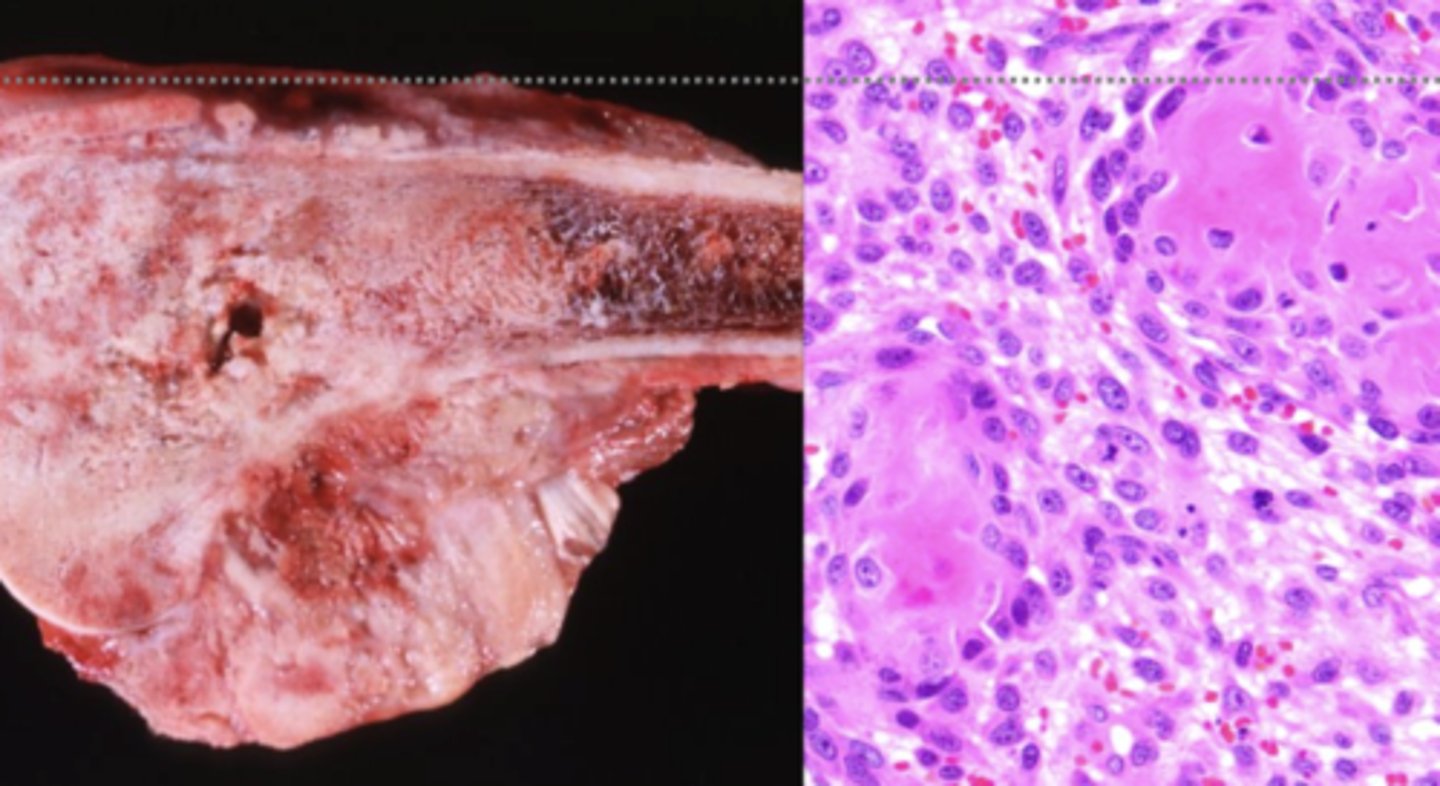

Osteosarcoma

What kind of tumor is this?